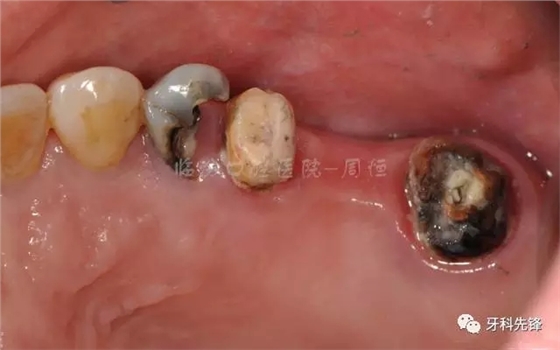

圖3術(shù)前頜面照

640.webp (4).jpg